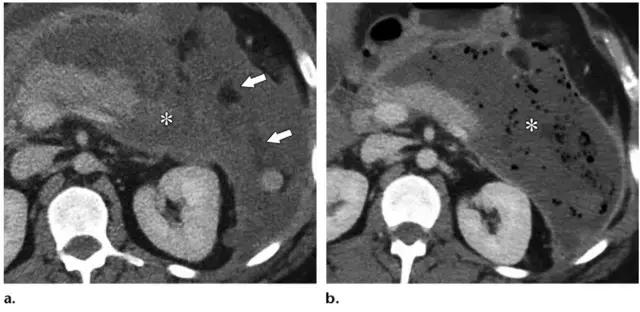

胰腺型:仅占 5%,没有胰周坏死物。在发病的前几天胰腺可仅表现为水肿,局限或弥漫性低强化,可能很难与 IEP 相鉴别,在这些病例中,在发病 5~7 天后再次行 CT 增强扫描可以提高诊断坏死性胰腺炎的准确率。

图 3 坏死性胰腺炎亚型在增强轴位 CT 的表现。a 胰腺和胰周同时受累的 58 岁女性患者,胰体无强化(*),正常强化的胰尾(黑箭头),小网膜囊内 ANC(白箭头)。b 仅胰周受累的 18 岁男性患者,可见一周为大片不均质密度(箭头),和 ANC 相符。胰腺实质密度正常(*)。c 仅胰腺实质受累的 33 岁男性患者,可见大片局限无强化的胰腺实质和脂肪密度(*),诊断为 WON。仅周边可见少量残余强化的胰腺实质(箭头)